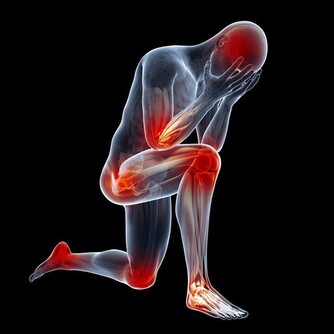

如放療、化療時,配合食補,往往能提高機體對化療、放療的耐受力,保護骨髓功能或促進骨髓功能恢復,改善造血作用,協助放療、化療發揮更大的作用。再者,許多食物本身亦有抗腫瘤的作用,如魚腥草、姬松茸、核桃、等。